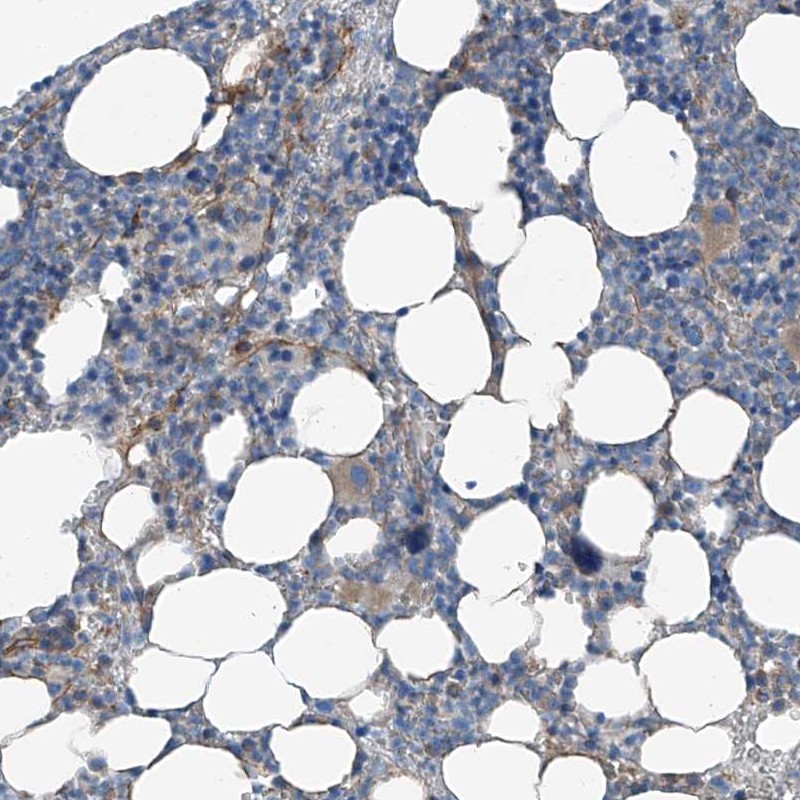

Immunohistochemical staining of human bone marrow shows weak positivity in hematopoietic cells.